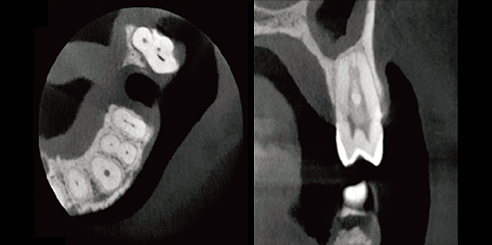

High-Resolution Dental CBCT Imaging

The system achieves image resolutions up to 2.0 lp/mm with a voxel size range of 0.05 – 0.25 mm.

Its 0.5 mm small focus tube guarantees smooth, stable, and reliable scans.

Furthermore, the high-definition image output ensures accurate diagnosis and confident treatment planning.

0.5mm small focus tube ensures outstanding image quality.

Resolution up to 2.0lp/mm, voxel size of 0.25~0.05 mm optional.

Furthermore, Panoramic Images are Reconstructed from 3D Dental CBCT data for clearer visualization